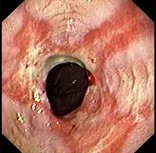

(单选题)胃镜检查如下图,诊断首先考虑()。

A:食管癌

B:贲门失迟缓症

C:幽门梗阻

D:反流性食管炎并食管狭窄

E:Barrett食管